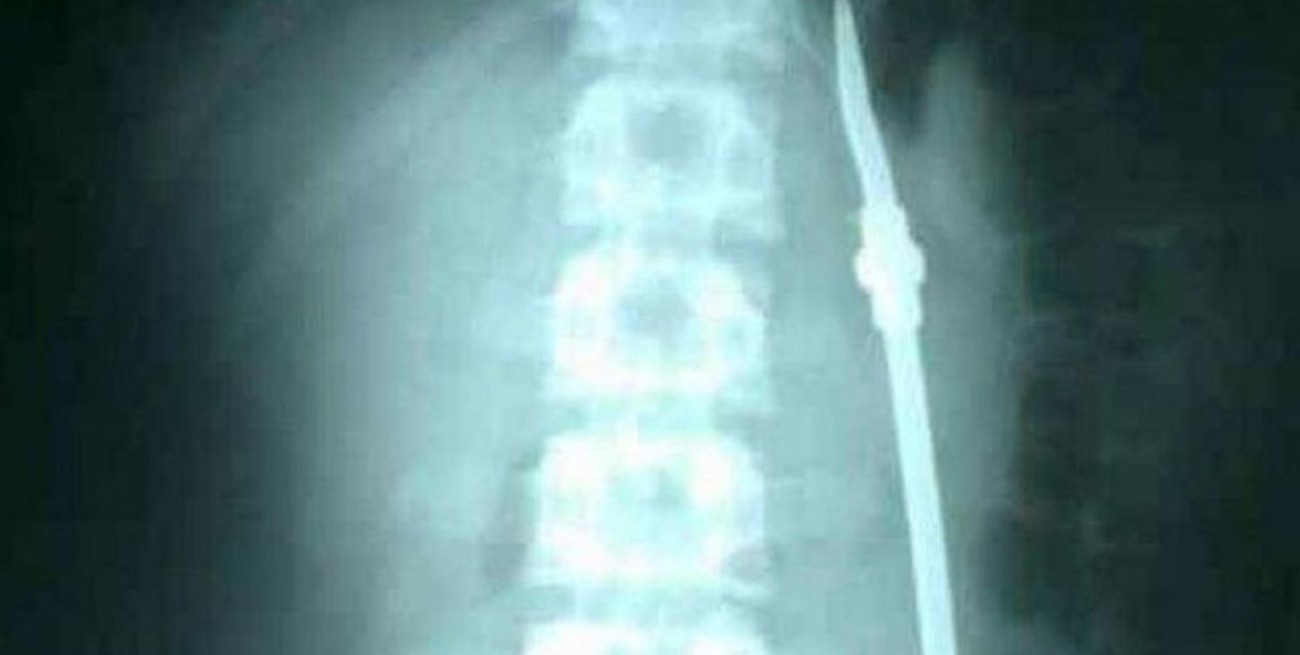

Luego de algunos estudios, los médicos detectaron que el joven efectivamente se había tragado una bombilla, pero fue intervenido quince días después. Cuando finalizó la operación, el detenido aprovechó un descuido de la custodia y se fugó.